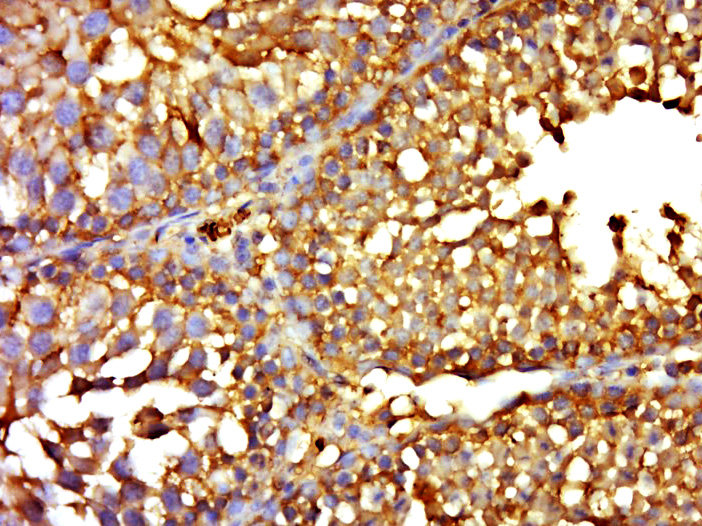

| 产品应用 | IHC-P=1:100-500, IHC-F=1:100-500, IF=1:100-500 Not yet tested in other applications. |

| {IHC-P} | {1:100-500} |

文献和实验:使用 Anti-phospho-Akt (Ser473) Rabbit mAb 对石蜡包埋的人乳腺癌组织进行免疫组织化学分析。(图 A)使用免疫组化试剂盒M&R HRP/DAB Detection IHC Kit,抗体 1:100 稀释;(图 B) 采用普通免疫组化试剂盒,抗体 1:25 稀释。 图 6 免疫组化实验检测 Erk1/2 表达 注:使用 Anti-Erk1/2 Mouse mAb与p44/42 MAPK (Erk1/2)Rabbit mAb 对正常小鼠心脏组织进行免疫